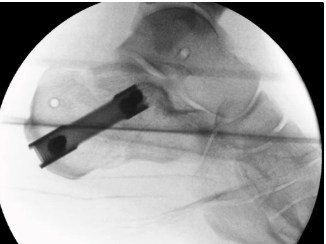

Percutaneous Fixation

Technique

Needs to be performed 3 - 5 days after injury while fracture fragments mobile

- 287 displaced intra-articular fractures

- MUA / Gissane spike percutanous reduction / K wire fixation

- 72% good or excellent results

- 1.7% deep infection, 7% superficial infection